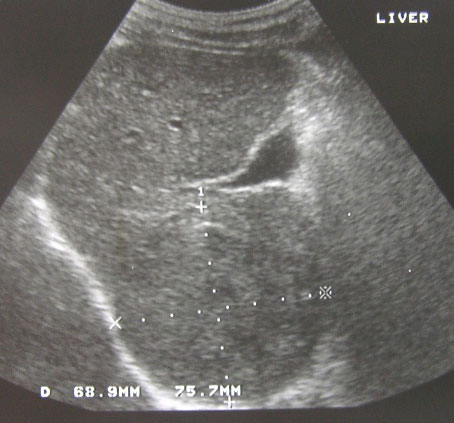

His problem started in late December 2011 when AS felt gastric-like pain in the stomach. An ultrasound at a hospital in his hometown indicated a possibility of gallbladder infection.

A whole body PET / CT on 2 February 2012 revealed left hepatic lobe mass, measuring 3.2 x 2.6 cm (picture below).

2-Feb-12-before-surgery